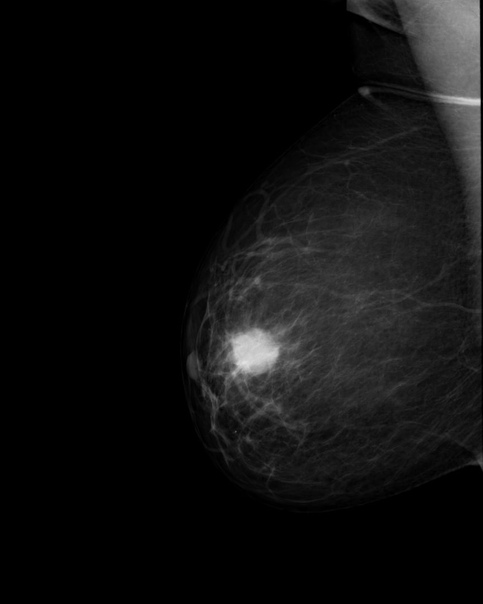

Сделать УЗИ молочных желез можно в качестве первичной диагностики и для уточнения уже предполагаемого диагноза. Метод основывается на способности высокочастотных ультразвуковых волн с различной скоростью отражаться от тканей с разной плотностью.

С помощью ультразвуковой диагностики можно обнаружить следующие заболевания:

- рак;

кальцинаты.